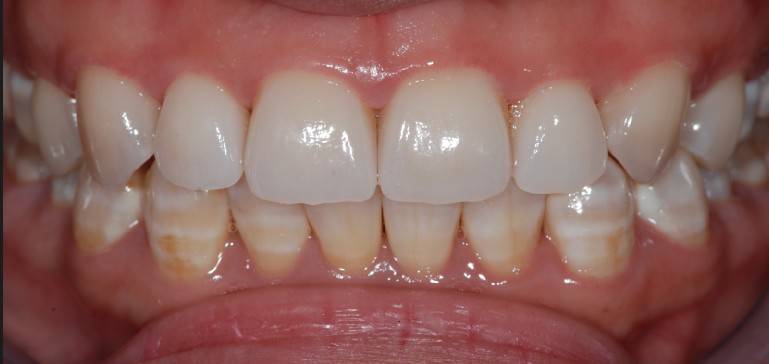

在口腔摄影里,因为拍摄环境的不同,所以需要黑板来增加摄影的成功率。黑色的物体可以吸收多余的干扰光,不仅能使主体颜色更加鲜明正确,还能与主体形成强烈的对比关系。

干货集结:

快门 1/125 、 光圈 F25 、 ISO 100

拍摄主体面向光源,不可多反光

比色板与牙齿保持于同一水平线